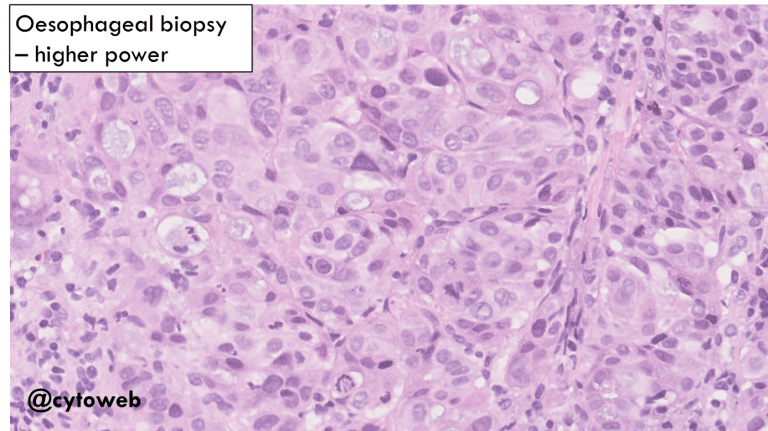

The malignant cells show features of adenocarcinoma.

- Metastatic malignancy: This is the favoured diagnosis as a second distinct population of benign thyroid cells are admixed with the carcinoma (see below).

Possible primary sources of a metastatic adenocarcinoma to the thyroid to consider:

- Lung adenocarcinoma

- Renal cell carcinoma (not likely the clear cell type)

- Breast carcinoma (invasive carcinoma of no special type)

- Gastrointestinal tract/pancreatobiliary adenocarcinoma

Knowledge of relevant clinical history and immunocytochemistry on cell block would be very helpful in the DDx.